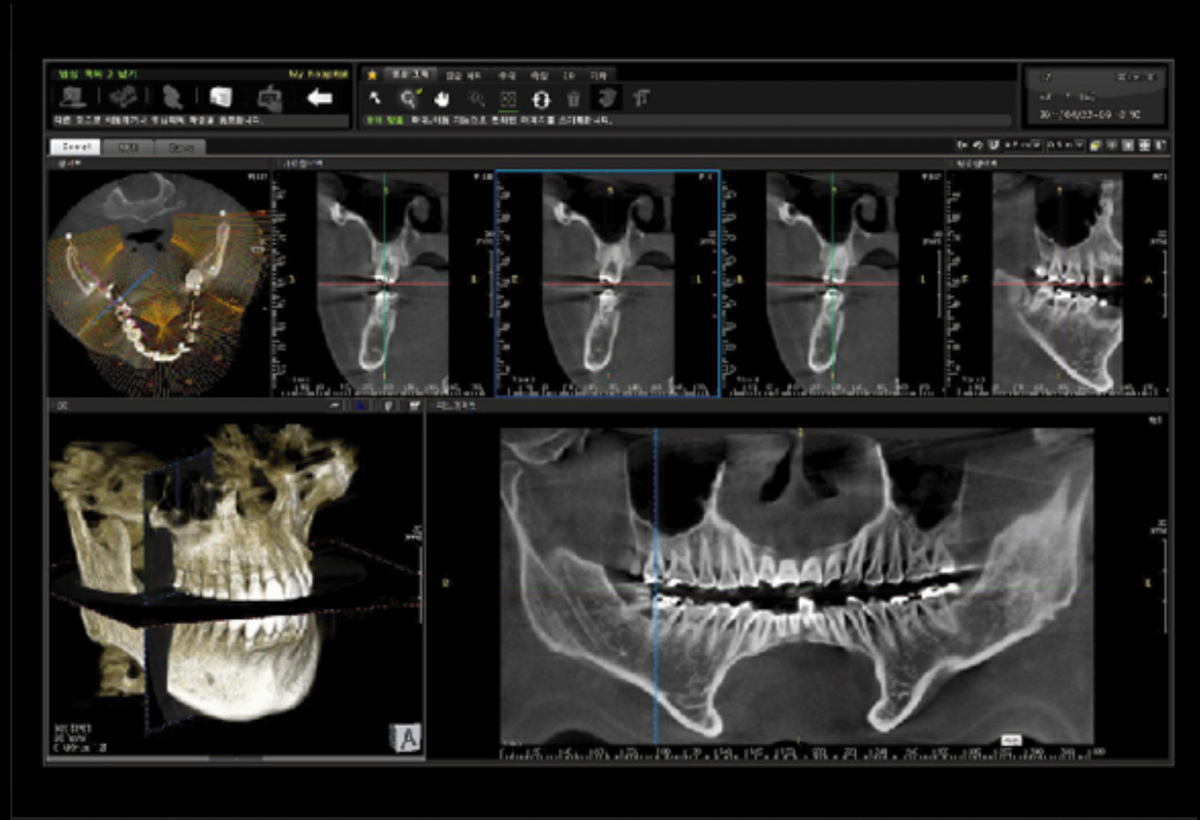

Немаловажным, а может главным вопросом, является универсальность программы-просмотровщика, в которой будут работать врачи-стоматологи. У Papaya 3D есть два варианта программ: Triana и OnDemand3D. Оба просмотровщика обладают схожим интерфейсом и имеют самые важные опции, а именно:

Triana.jpg  OnDemand3D.jpg

• режим MPR (многоплоскостная реконструкция). Именно здесь выстраивается интересующий участок челюсти или зуба для анализа.

• панорамный реформат. Возможность постройки классической и сегментарной панорамы позволяет продемонстрировать план лечения пациенту, а также оценить расположение анатомических структур на боковых кросс-секциях.

• модуль дентальной имплантации. Возможность виртуальной установки дентального имплантата с анализом окружающей костной ткани. В библиотеке представлен широкий спектр имплантологических систем с индивидуальной прорисовкой имплантата.

• выделение нижнечелюстного канала позволяет продемонстрировать расположение важного анатомического образования и определить зону безопасности при проведении лечения.

• функции плотности, линейных измерений и угла – необходимы для получения полноценной информации для последующего лечения.

• 3D режим – показывает трехмерную модель челюсти с целью определения аномалий, деформация, а также визуализации виртуальных имплантатов.

triana3.jpg triana4.jpg triana5.jpg

OnDemand3D (1).jpg OnDemand3D (2).jpg OnDemand3D 1.jpg

Таким образом обе программы являются простыми в пользовании, но обладающими обширным спектром возможностей для диагностики любыми специалистами-стоматологами. В данные программы происходит загрузка классических файлов DICOM 3.0, которые являются общепринятым форматом записи данных пациента. Это важный момент, так как позволяют врачу, имеющему полную версию программы загружать даже сторонние исследования и просматривать их в этих программах. Простота в освоении этих программ позволяет даже специалисту, не работающему раннее с этими программами, быстро адаптироваться и получить качественную информацию. Возможность выгрузки STL-файла дополнительно создает возможность интегрировать данные с цифровым ортопедическим протоколом.